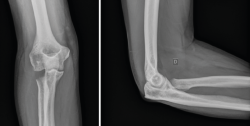

Figura 8. Ejemplos de fracturas de olécranon en 2 partes (tipo 2A) fijadas con obenque (A y B) y fracturas de tipo 2B fijadas con distintos diseños de placas (C y D).